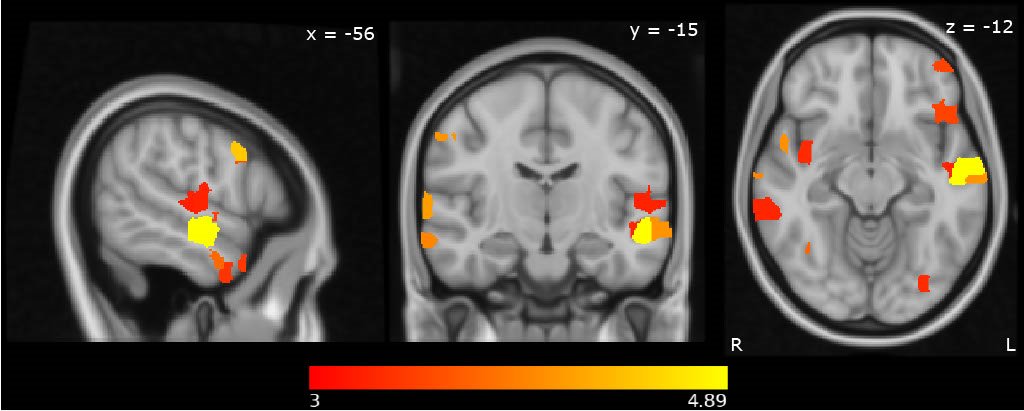

Now also seems like a good time to announce here that I’m taking a clinical grad student(s) this year. If you’re interested in how reward processing develops in the young brain, or in genetic syndromes, come talk to me! I’ll be at the @ABCTAutism happy hour tonight.